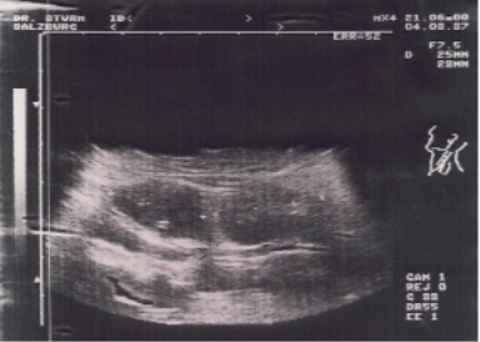

| Untersuchung | 2 hochgradig verdächtige Lymphknoten am Hals | ||||||||||||||||||||||||||||||||||||||||||||||||||||||||||||||||

Der Ultraschalldiagnostik kommt, vor allem auch im HNO Bereich, dank ihrem Vorteil der Nichtinvasivität, aber auch dank laufender technischer Entwicklung, eine immer größere Bedeutung in der medizinischen Diagnostik zu. Wir führen in unserer Praxis Ultraschalluntersuchungen der Halsweichteile durch. Bei einer unklaren Schwellung im Halsbereich ist die Sonographie die erste und eine der aussagekräftigsten Untersuchungsmethoden. Sollte ein verdächtiger Befund erhoben werden, wird eine ultraschallkontrollierte Feinnadelpunktion als weitere diagnostische Maßnahme durchgeführt. So lässt sich mit relativ geringem Aufwand eine genau Diagnose der Halsschwellung stellen und es können rasch, falls nötig, weitere Schritte in die Wege geleitet werden. | |||||||||||||||||||||||||||||||||||||||||||||||||||||||||||||||||

| Folgende Veränderungen lassen sich mit Hilfe der Halssonographie sehr gut diagnostizieren: | |||||||||||||||||||||||||||||||||||||||||||||||||||||||||||||||||

Veränderungen der Schilddrüse mediane und laterale Halszysten Weichteiltumore am Hals Steinerkrankungen der Speicheldrüsen Tumore der Speicheldrüsen Lymphknotenentzündungen bösartige Lymphknotenerkrankungen Lymphknotenmetastasen | ||||||||||||||||||||||||||||||||||||||||||||||||||||||||||||||||